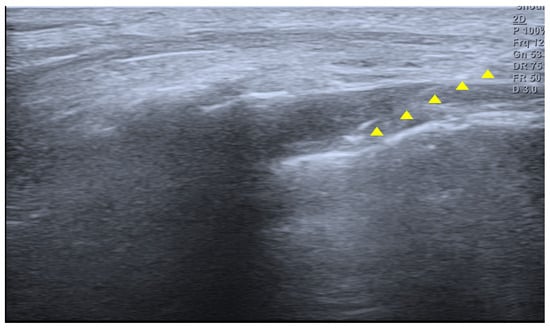

A 14-year-old girl developed coccygeal pain following a fall inside a bus six months earlier. At that time, she was diagnosed with sacrococcygeal dislocation at an outside hospital and was prescribed acetaminophen and NSAIDs, which maintained her symptoms at a Numerical Rating Scale (NRS) score of approximately 3. However, one month prior to presentation, she sustained a second fall to the same area, after which her pain worsened despite continued pharmacologic treatment, reaching an NRS score of 6. She was therefore referred to our pain clinic. The radiographs obtained at the time of the initial injury were unavailable. Radiography performed at our institution demonstrated anterior angulation of the coccyx (Figure 1). Physical examination revealed tenderness over the sacrum and coccyx. The patient was able to sit but could not remain seated for prolonged periods due to pain and reported worsening pain upon standing. No cutaneous abnormalities or swelling were noted over the coccygeal region. She denied defecation-related pain. For pain control, an ultrasound-guided caudal epidural block was performed (Figure 2). Prior to the procedure, the patient and guardians received a detailed explanation of the block. As the patient was cooperative and fully understood the process, the procedure was performed without sedation or anxiolysis, using verbal reassurance alone. Under sterile conditions, the patient was positioned prone, and the sacral hiatus was identified using ultrasound. After local anesthesia of the skin at the needle insertion site, a butterfly catheter was advanced toward the sacral hiatus under an out-of-plane view, traversing the sacrococcygeal ligament. The needle was then redirected in-plane into the epidural space. A mixture of 1 mL of 2% mepivacaine, 8 mL of 0.9% normal saline, and 5 mg of dexamethasone was injected. At the 2-week follow-up, although the qualitative character of pain remained similar, the patient reported an increased ability to remain seated and a reduced frequency of pain when standing. Her pain intensity decreased significantly to an NRS score of 2, accompanied by noticeable functional improvement. At the 2-month follow-up, her pain remained at an NRS score of 2, and she maintained a level of daily functioning without significant limitations.

Figure 2. Ultrasound image of the sacral hiatus during caudal epidural block. The needle is seen advancing through the sacrococcygeal ligament into the caudal epidural space under real-time guidance (yellow triangle indicates the needle).